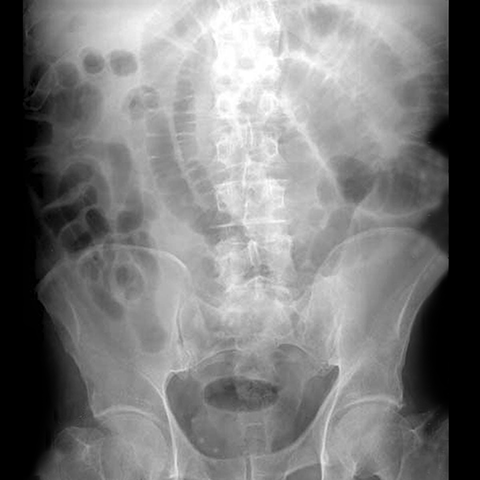

27 year-old male with a history of an appendectomy presents with nausea, vomiting, colicky abdominal pain, and diarrhea. [1 of 3]